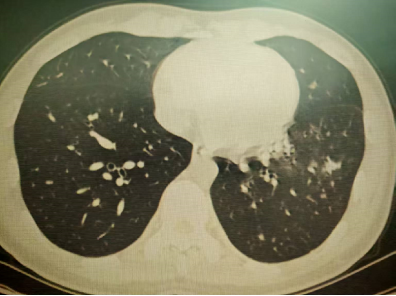

以上是他的胸部CT影像,主要表现为左下肺炎症,片絮影+磨玻璃影。

肺部感染的影像学特征

多发性结节伴快速进展

CT表现为双肺多发实性结节(直径0.5-3cm),结节边缘可见毛刺征及分叶征,特征性表现为短期内体积呈几何级数增长(如1周内增大10倍),需与转移瘤、结核球等鉴别。

混合性密度影与胸腔积液

40%病例出现磨玻璃影与实变影共存,部分结节中央可见液化坏死;30%伴单侧渗出性胸腔积液,积液分析呈渗出性但培养阴性,此表现易误诊为脓胸。